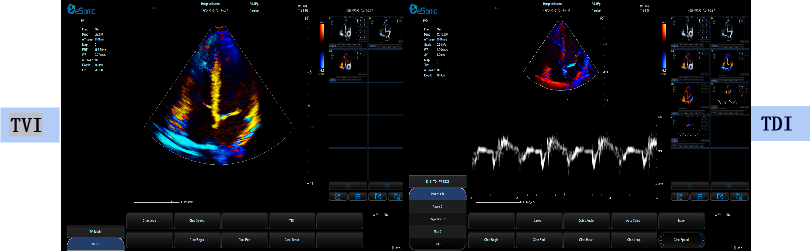

相关技术优势:eHertz的高敏感血流,提高血流敏感性,降低噪声干扰

eHertz优异的TDI表现- 图像非常干净

组织多普勒

包含多种模式

可对室壁运动进行速度、加速度的测量和分析

可观察心肌运动、定量分析心肌的运动速度变化,检测心肌供血情况

可评价早期的舒张功能